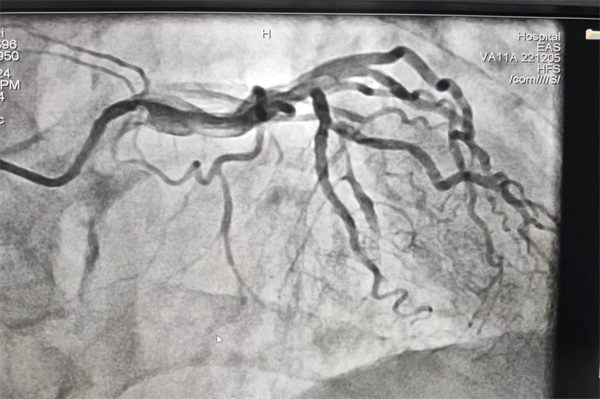

患者李先生,反复胸闷不适20余年,并伴有冷汗、心前区压榨感,近期患者胸闷感加重,在家人陪同下至犍为县人民医院心血管内科住院治疗。入院后行冠状动脉造影提示前降支弥漫性长病变,为重度狭窄伴严重钙化。

PCI术前造影